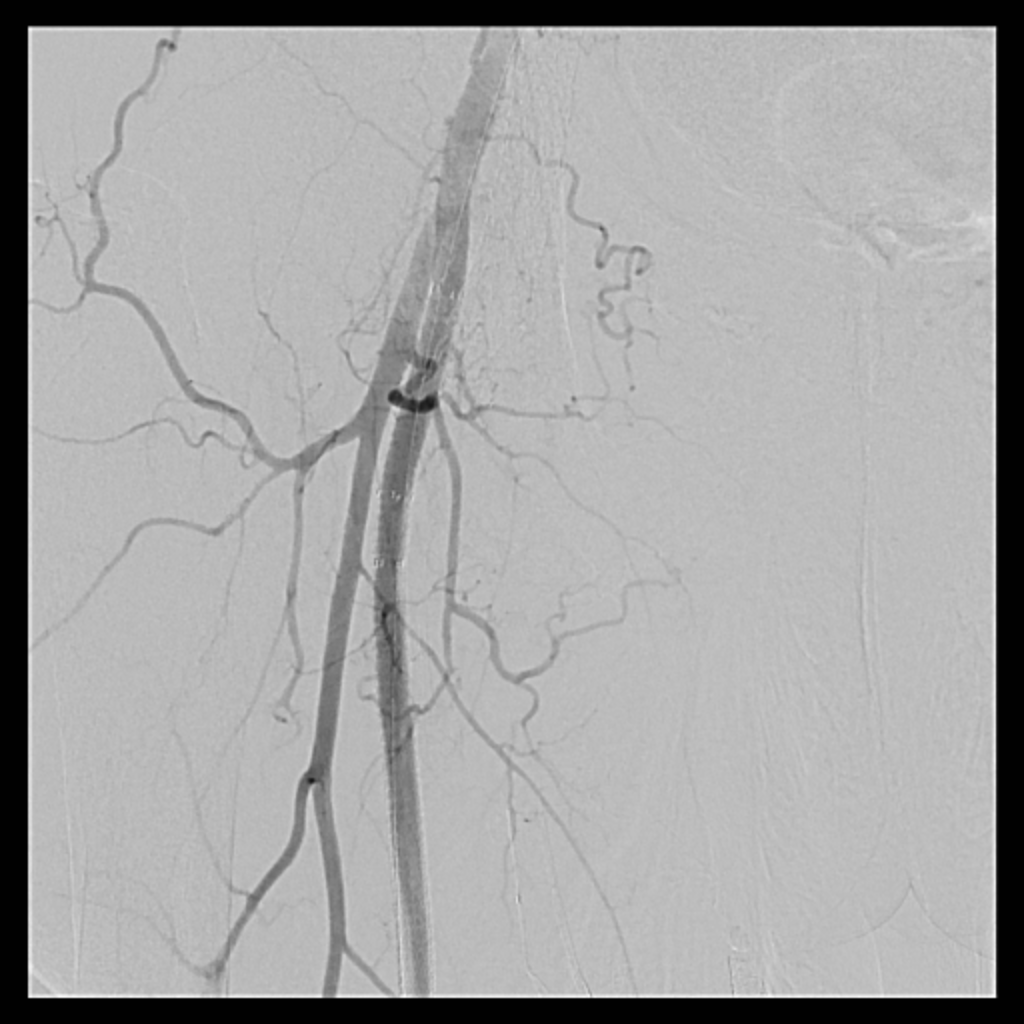

Venous access was obtained and venography confirmed heavy thrombus burden; therefore, the initial 6 Fr sheath was upsized to a 9 Fr sheath. Two Terumo stiff wires were advanced into the IVC to secure stable access. Mechanical thrombectomy using the Boston Scientific AngioJet system was performed from the right iliac vein to the right common femoral vein. During venography, unexpected early arterial opacification suggested an iatrogenic artery-to-vein fistula. Iliac angiography was then performed, revealing a total occlusion of the right common iliac artery with collateral reconstitution. To restore arterial flow and seal the fistula, a contralateral approach was used. A wire successfully crossed the occluded segment into the true lumen, followed by deployment of a covered stent. Final angiography showed complete closure of the fistula and restored antegrade arterial flow without distal embolization. The patient remained hemodynamically stable.

This case demonstrates that venous interventions may unexpectedly expose silent arterial disease. Rapid recognition of arterial opacification led to timely management of an iatrogenic artery-to-vein fistula and unrecognized arterial occlusion. Endovascular therapy enabled simultaneous rescue and reconstruction with excellent immediate outcomes.